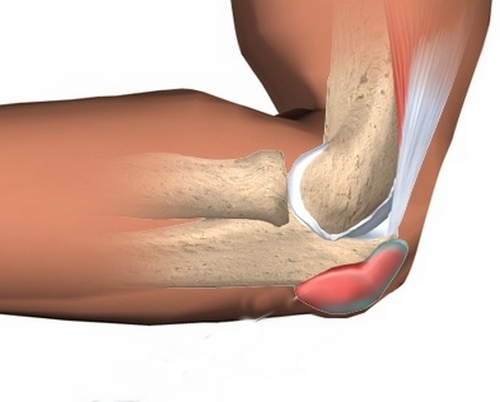

Бурсит локтевого отростка

На верхушке локтевого сочленения располагается подкожная сумка, которая заполнена синовиальной жидкость. Если произошла травма, либо имеет место быть постоянное трение этой области о стол, эта сумка может воспаляться. Подобный патологический процесс может развиться на фоне ревматоидного артрита и подагры.

Диагностика бурсита локтевого отростка не представляет трудностей: при согнутой руке на суставе появляется округлое образование, которое имеет мягкую консистенцию и отличается малоболезненностью. Если развивается бурсит гнойного характера, то пациент будет жаловаться на сильные боли в локтевом суставе, отечность и покраснение кожи в месте поражения.